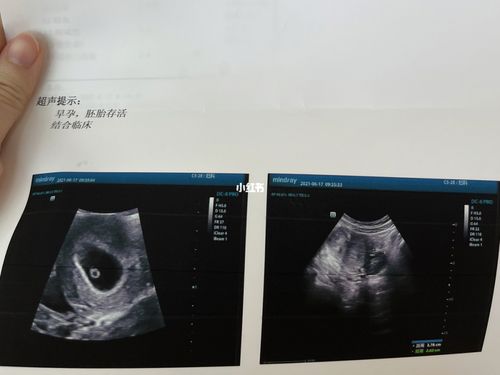

胎芽是什么样的图片,怀男孩孕囊图片

新鲜的胎心胎芽来啦!

[试管婴儿]移植第30天,成功出现胎心胎芽

胎心胎芽图片

胎心胎芽真实图片

胎芽胎心放大图片